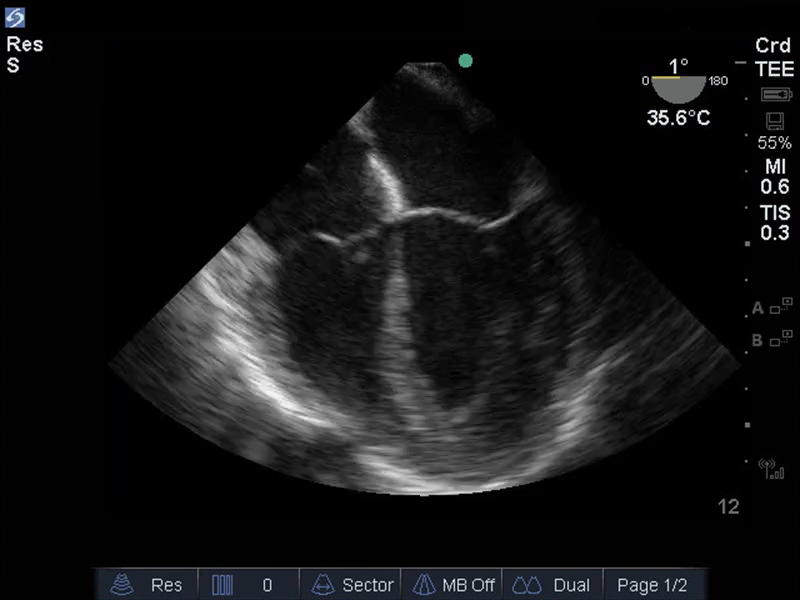

TEE食道中位4室断面の画像